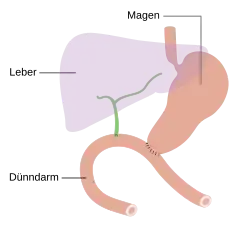

- Operationsvarianten

-

Pylorus-erhaltende Teilresektion

Pylorus-erhaltende Teilresektion -

Duodenopankreatektomie nach Whipple

Duodenopankreatektomie nach Whipple -

Endzustand nach Whipple-Operation

Endzustand nach Whipple-Operation -

Totale Pankreasresektion

Totale Pankreasresektion -

Endzustand nach Totalresektion

Endzustand nach Totalresektion